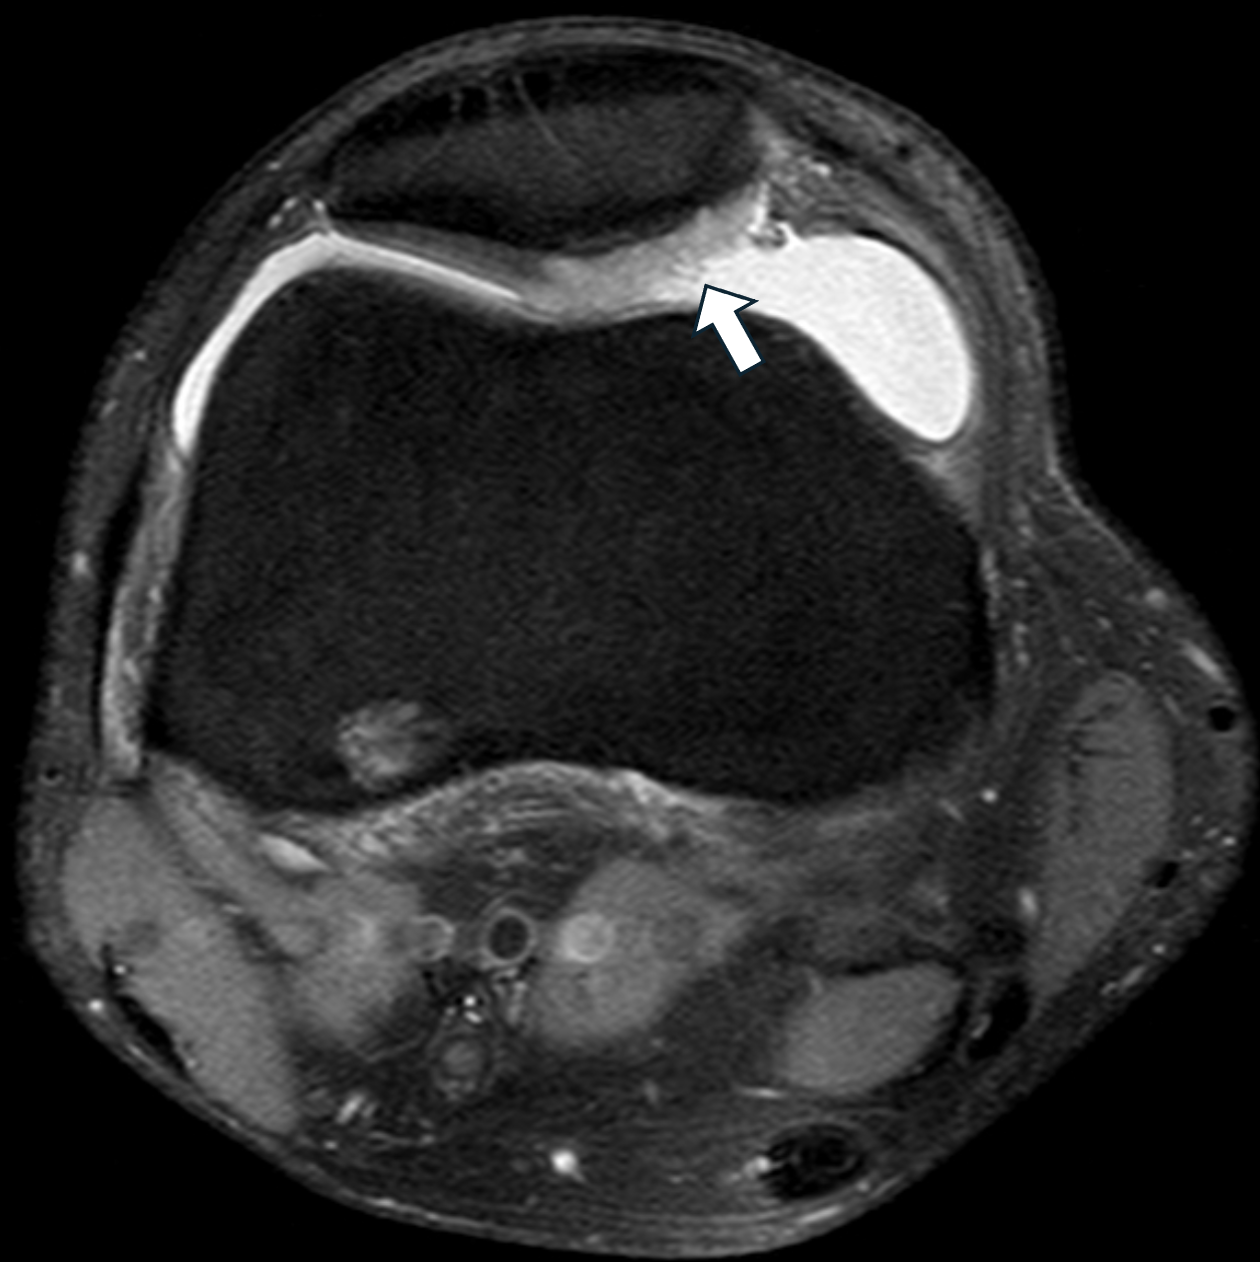

Was für eine Pathologie ist auf dem vorliegenden MRT-Bild markiert?